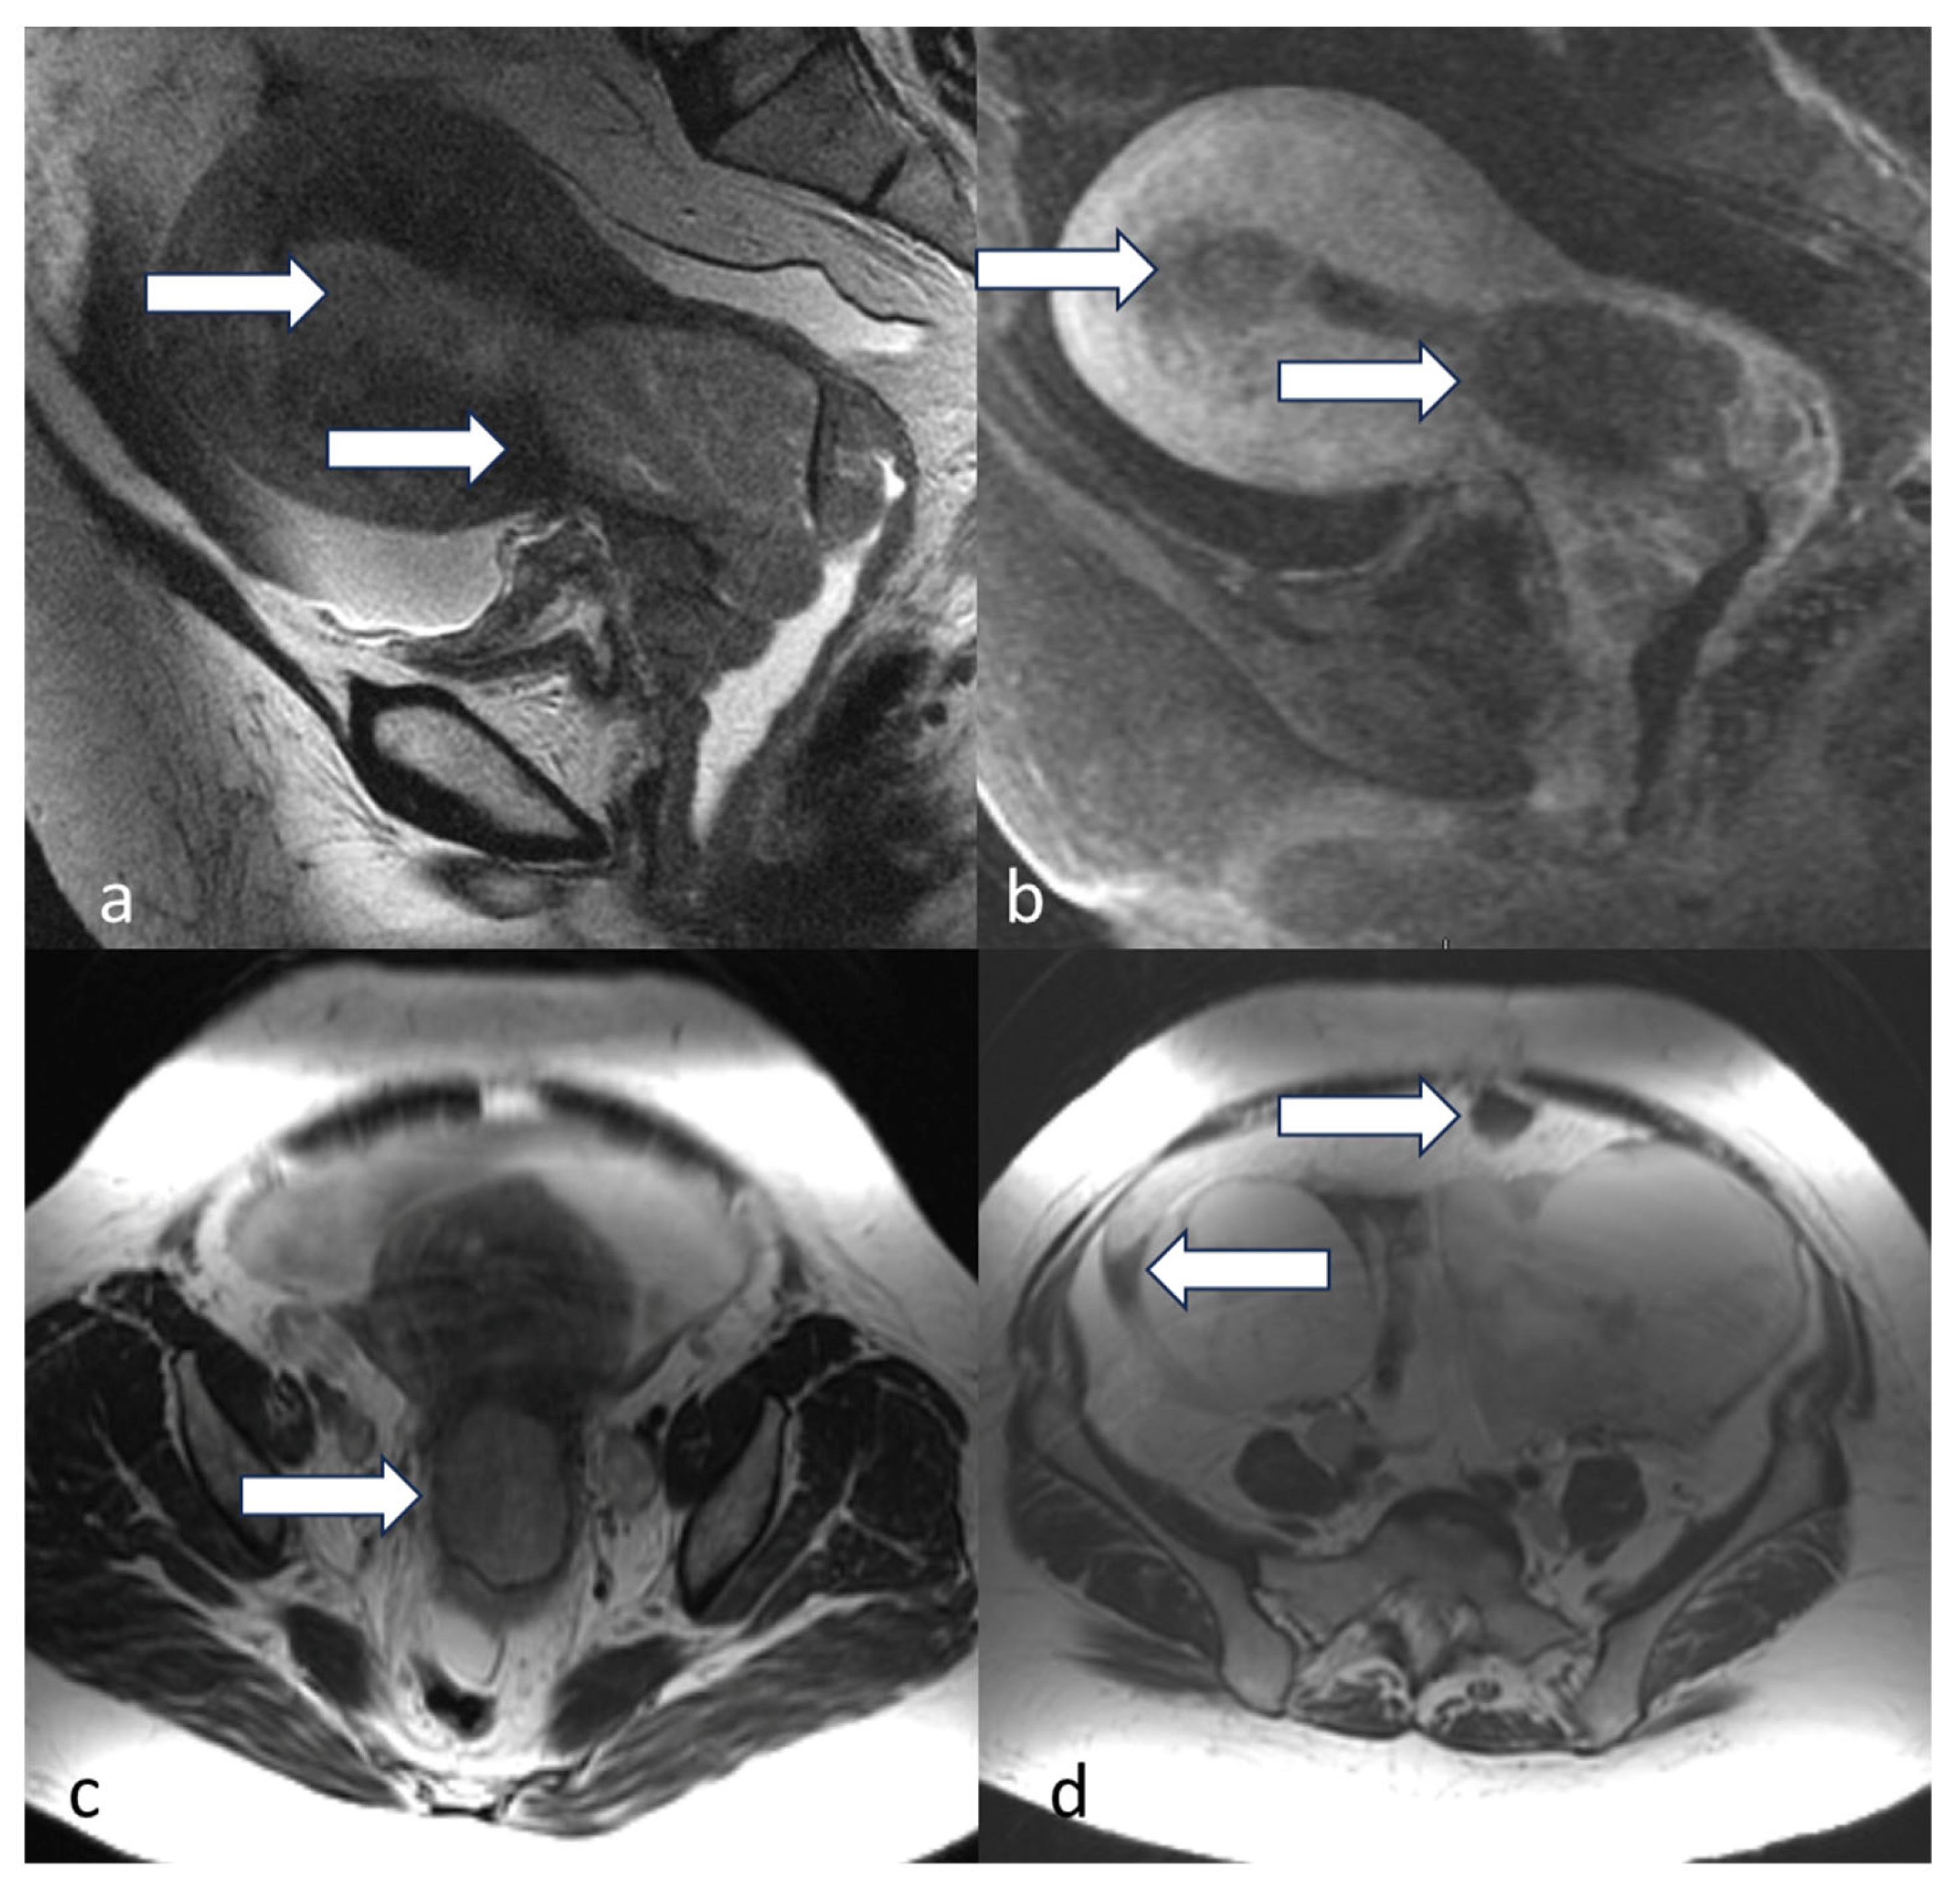

5.3. Magnetic Resonance Imaging (MRI)

- Maheshwari, E.; Nougaret, S.; Stein, E.B.; Rauch, G.M.; Hwang, K.-P.; Stafford, R.J.; Klopp, A.H.; Soliman, P.T.; Maturen, K.E.; Rockall, A.G.; et al. Update on MRI in Evaluation and Treatment of Endometrial Cancer. RadioGraphics 2022, 42, 2112–2130. [Google Scholar] [CrossRef] [PubMed]

- Neves, T.R.; Correia, M.T.; Serrado, M.A.; Horta, M.; Caetano, A.P.; Cunha, T.M. Staging of Endometrial Cancer Using Fusion T2-Weighted Images with Diffusion-Weighted Images: A Way to Avoid Gadolinium? Cancers 2022, 14, 384. [Google Scholar] [CrossRef] [PubMed]

- Nougaret, S.; Horta, M.; Sala, E.; Lakhman, Y.; Thomassin-Naggara, I.; Kido, A.; Masselli, G.; Bharwani, N.; Sadowski, E.; Ertmer, A.; et al. Endometrial Cancer MRI staging: Updated Guidelines of the European Society of Urogenital Radiology. Eur. Radiol. 2019, 29, 792–805. [Google Scholar] [CrossRef]